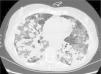

We report the case of a 57-year-old woman, former smoker, with a history of non-pathological cervical and axillary lymphadenopathies, non-necrotizing granulomatous mastitis and acute dorsal myelopathy. She was admitted for bronchopneumonia, and underwent bronchoscopy with transbronchial biopsies, which were inconclusive, and bronchoalveolar lavage (BAL) showing 65% lymphocytes and a normal CD4/CD8 ratio. The patient was readmitted due to right pleural effusion, categorized as lymphocytic exudate with no malignant cellularity, hepatosplenomegaly, and signs of pulmonary hypertension. Low levels of IgG subclasses were reported and treatment was initiated with prednisone. The patient subsequently developed dyspnea, anorexia and asthenia. Chest computed tomography showed peribronchial pulmonary nodules with undefined borders, air bronchogram sign, and tendency to converge into large masses in the lower lobes. These masses were surrounded by ground glass opacities and mediastinal lymphadenopathies, indicative of lymphomatoid granulomatosis. Ground glass opacities and lymphadenopathies, however, are not typical of lymphomatoid granulomatosis, and may have been associated with the patient's smoking habit (Fig. 1). Lung function tests showed moderate restriction, with 36% diffusion, and laboratory reports revealed leukopenia due to lymphopenia. A bone marrow biopsy and a second bronchoscopy were performed, from which BAL showed predominant lymphocytes and a normal CD4/CD8 ratio. No additional data could be obtained from biopsy of a paratracheal lymphadenopathy. Culture and cytology were negative. A lung biopsy was obtained, after which the patient showed clinical and radiological worsening.